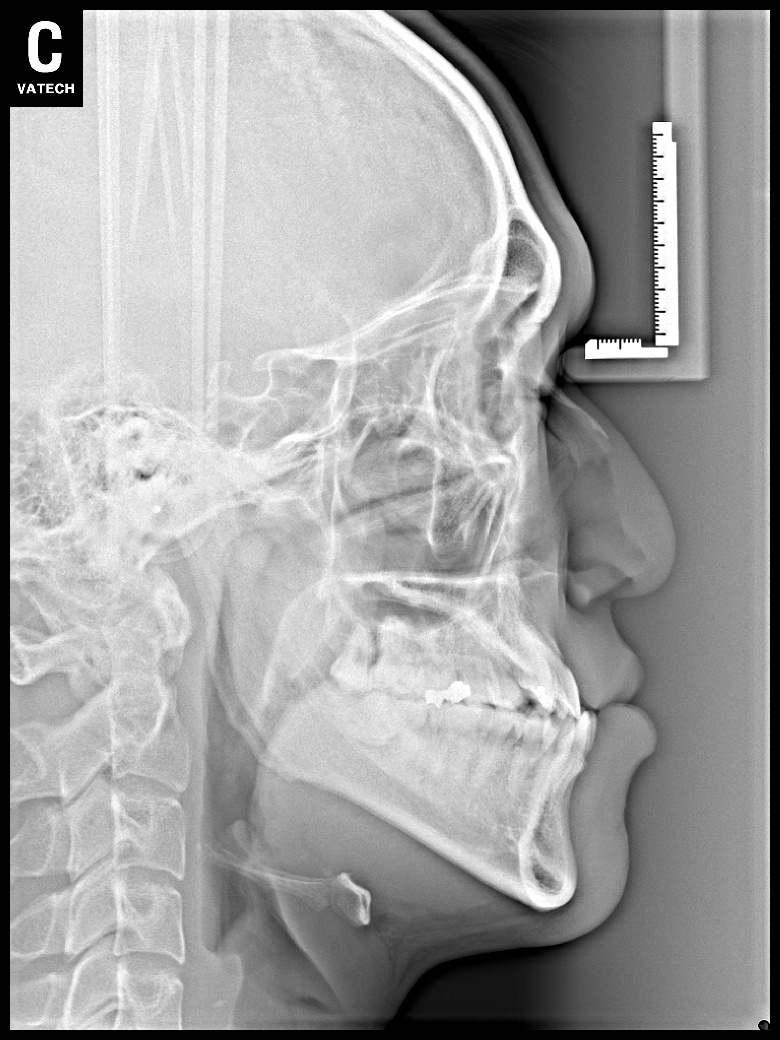

치료 후 사진입니다.